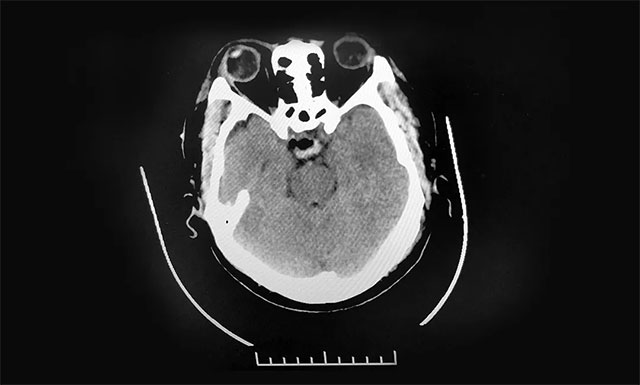

猶豫之后,他懷著忐忑的心情去當?shù)蒯t(yī)院檢查,頭顱CT提示:鞍區(qū)占位,考慮垂體瘤復(fù)發(fā),醫(yī)生建議轉(zhuǎn)上級醫(yī)院治療。隨后,他慕名來到上海藍十字腦科醫(yī)院尋求進一步治療。

▲ 術(shù)后影像顯示腫瘤被切除